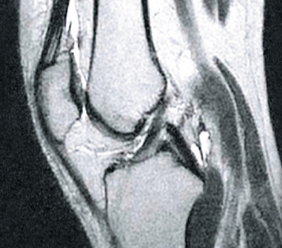

На снимката вляво можете да видите празни пространства в ставната капсула, образувани в резултат на прекомерна хидратация на тъканта. След терапия структурата на синовиалната течност се възстановява (снимката вдясно), възвръща своята вискоеластична консистенция и плъзгащи се свойства. Костите са правилно "смазани", така че да не се търкат една в друга, тъй като омекотяващите функции на ставата са възстановени.